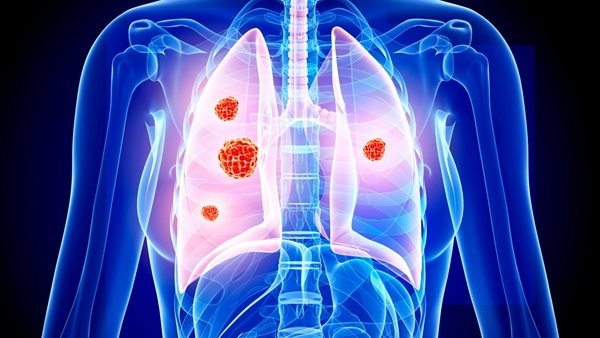

أعراض سرطان الرئة.. بينها علامة تظهر عند التحدث

يعد سرطان الرئة أكثر أشكال السرطان فتكًا في عدد من البلدان في أنحاء العالم، حيث يمثل أكثر من 20% من جميع وفيات السرطان كل عام.

أعراض سرطان الرئة

عادة لا تظهر أعراض سرطان الرئة في المراحل المبكرة من المرض.

لكن العلامات الأكثر شيوعًا لـ سرطان الرئة هي:

سعال لا يزول بعد 3 أسابيع.

سعال طويل الأمد يزداد سوءًا.

التهابات الصدر التي تستمر في العودة.

سعال الدم.

وجع أو ألم عند التنفس أو السعال.

ضيق التنفس المستمر.

التعب المستمر أو نقص الطاقة.

فقدان الشهية أو فقدان الوزن غير المبرر.

أعراض سرطان الرئة الأقل شيوعا

تشمل العلامات الأخرى الأقل شيوعًا لـ سرطان الرئة ما يلي:

تغيرات في مظهر الأصابع، مثل أن تصبح أكثر انحناءً أو أن تصبح أطرافها أكبر، ويُعرف هذا باسم تعجر الأصابع.

صعوبة في البلع، المعروف باسم عسر البلع، أو ألم عند البلع.

الصفير.

تورم الوجه أو الرقبة.

ألم مستمر في الصدر أو الكتف.